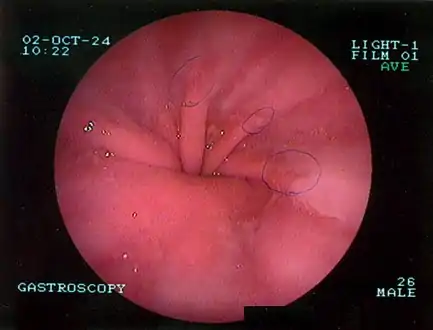

Diagnosis

The diagnosis of a hiatal hernia is typically made through an upper GI series, endoscopy, high resolution manometry, esophageal pH monitoring, and computed tomography (CT). Barium swallow as in upper GI series allows the size, location, stricture, stenosis of oesophagus to be seen. It can also evaluate the oesophageal movements. Endoscopy can analyse the esophageal internal surface for erosions, ulcers, and tumours.